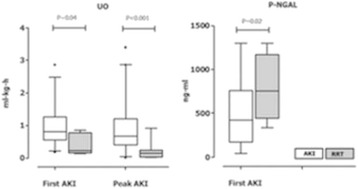

P182 - Plasma NGAL and urinary output: potential parameters for early initiation of renal replacement therapy

K. Maas, H. De Geus